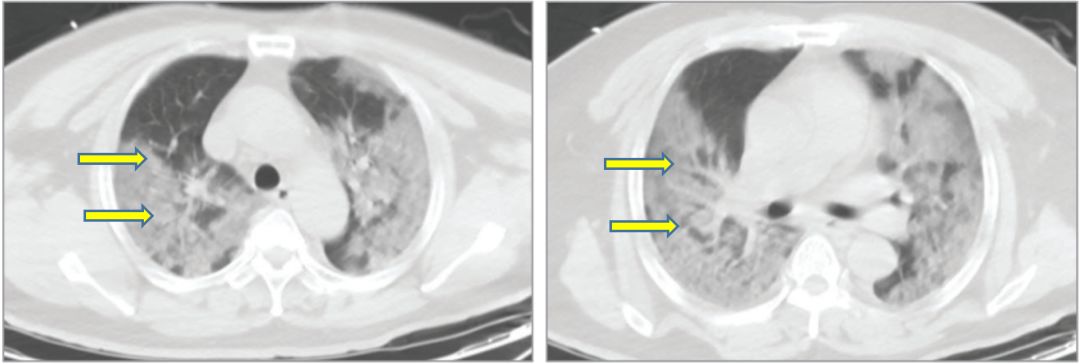

一旦形成细胞因子风暴,免疫系统不一定能杀死病毒,但是肯定会杀死大量肺的正常细胞,严重破坏肺的换气功能,在肺部CT上表现为大片白色,即“白肺”,患者会呼吸衰竭,直至缺氧死亡。

新型冠状肺炎患者的肺部CT,大片白色部分即受损的肺[7]